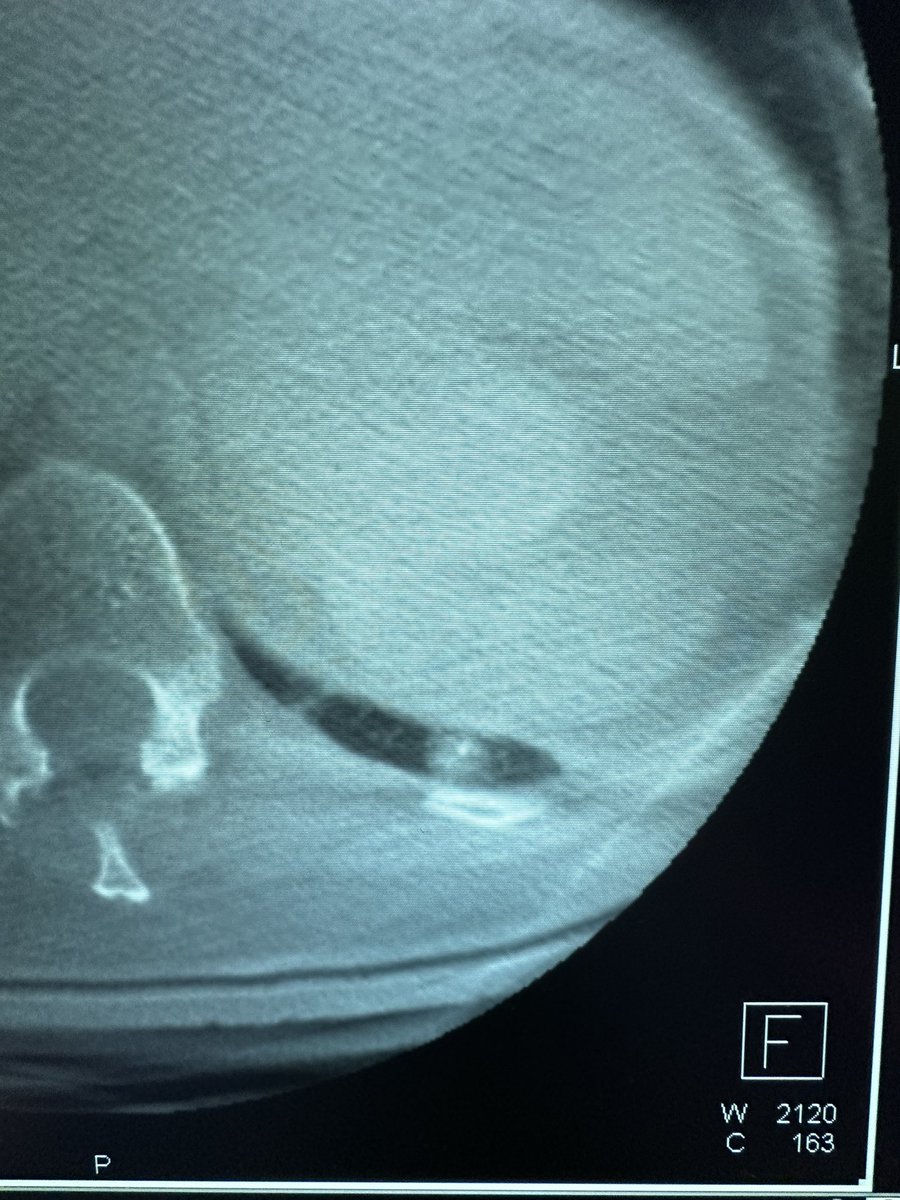

Bhadra & Condra CBCT Bronchoscopy

If you don't like the road you are on, pave a new one: Cone Beam CT Bronchoscopy.